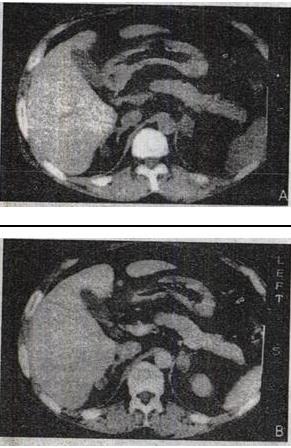

- 单项选择题3、 患者,男,43岁。头痛,头晕1年余。血压150/95mmHg。CT表现如图所示。最有可能的诊断是()。

A、肾上腺增生

B、肾上腺腺瘤

C、肾上腺腺癌

D、肾上腺囊肿

E、嗜铬细胞瘤